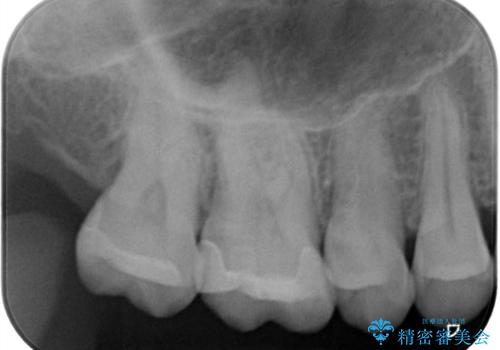

- 昔入れた金属の被せ物を白い物に変えたいと思い来院された患者様です。レントゲン等確認し審美的によく、強度のあるセラミックインレーにて治療いたしました。

審美的に良い補綴物に変わり満足いただきました。かみ合わせも問題なく快適に食事できているとのことでした。